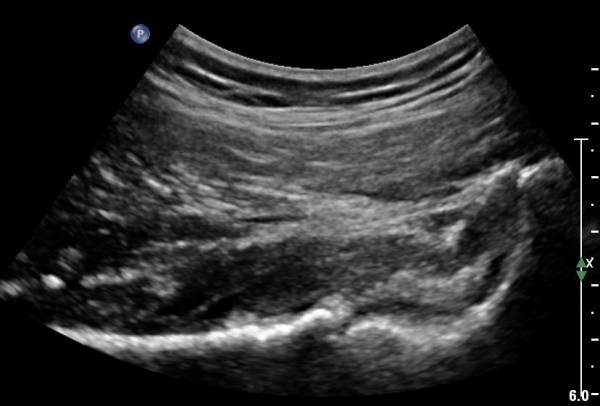

°í°üÀý À§, ¿ÜÃø¿¡¼­ ´ëÅðÁ÷±Ù Á¾´Ü¸é°Ë»ç»ó  ´ëÅðÁ÷±Ù °ðÀº ¼¶À¯(direct) ±â½ÃºÎ¿¡ ¹Ì¼¼ÇÑ

¼®È¸¼º º´º¯À» º¸À̳ª ÈûÁÙÀÇ Àú¿¡ÄÚ ºÎÁ¾Àº °üÂûµÇÁö ¾ÊÀ½.(»çÁø 3, 4)